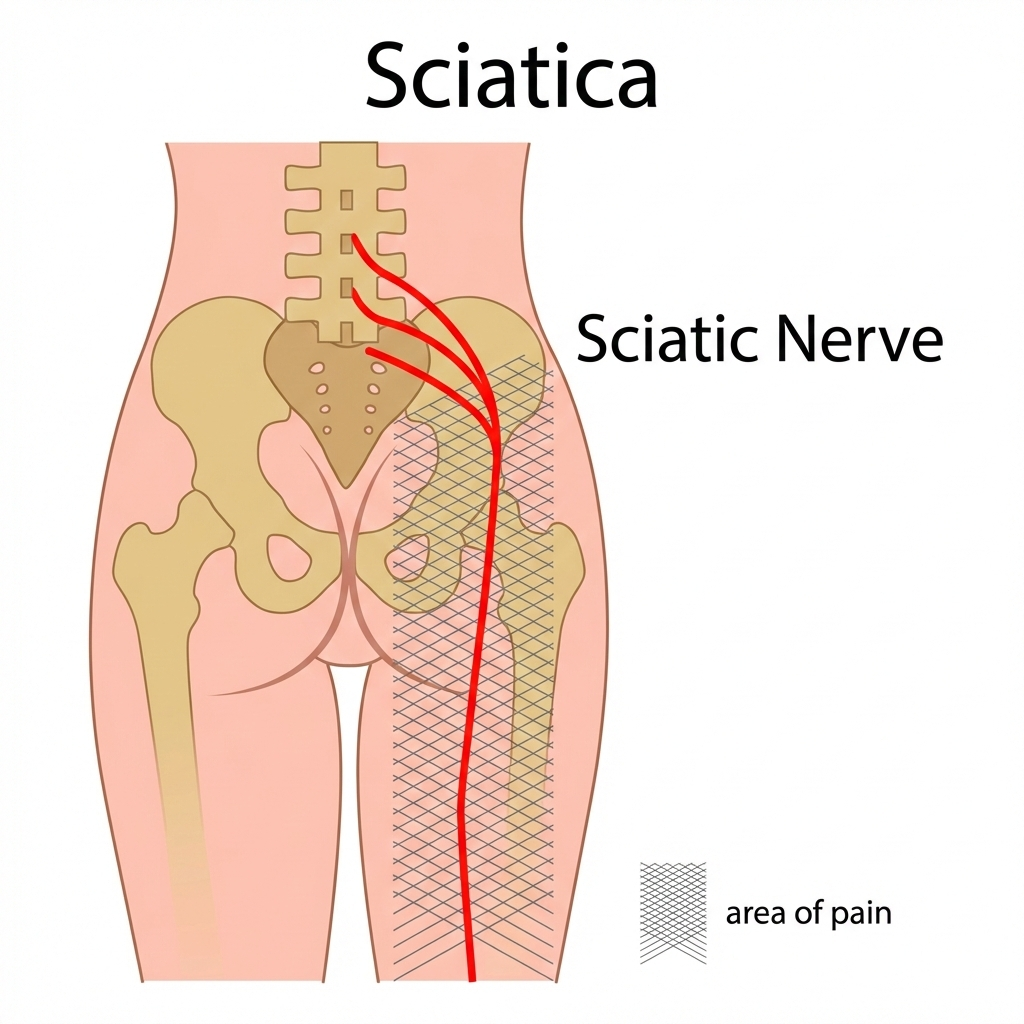

Facet Joint Arthritis (Very Common & Frequently Missed)

What are facet joints?

Facet joints are small stabilizing joints at the back of the spine that guide movement and bear load.

What happens in arthritis?

- Cartilage wears down

- Joint becomes inflamed and stiff

- Pain is typically one-sided

Key symptoms

- Right-sided lower back pain

- Pain worse on standing, twisting, or arching backward

- Pain improves on sitting or bending forward

- No true leg numbness (unless severe)

Also read : Why does my lower back hurt when sitting

Why it’s important

Facet joint arthritis is a leading cause of chronic unilateral lower back pain, especially in people over 35.